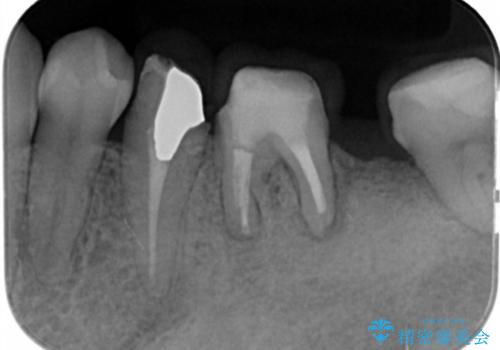

- 他院で根の治療まで終え、違和感が取れず相談に来院されました。

当該歯を精査したところ、歯根に破折が見られ抜歯を余儀なくされました。